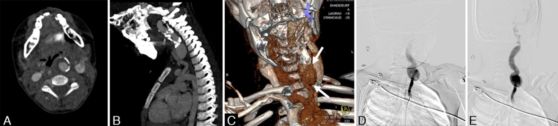

7.病例报道:一例对氯吡格雷不敏感的巨大颈段颈内动脉动脉瘤患儿的复合血管介入治疗

Hybrid vascular intervention for a giant cervical carotid artery aneurysm in a clopidogrel-hyporesponsive child.

DOI: 10.3171/2018.3.PEDS17669.

儿童颈内动脉(ICA)颅外段动脉瘤是一种罕见的动脉瘤,多采用外科手术治疗。作者报道了一例造成气道压迫的儿童ICA颅外段动脉瘤。治疗计划为先手术探查动脉瘤,术中矫正动脉迂曲,便于颈动脉重建失败后行血管内介入治疗。最后,作者采用分期复合治疗手段成功处理了该动脉瘤,即先外科矫正载瘤动脉迂曲,后置入支架。患儿耐受了该手术,无不良反应。术后5月的头颈部CTA显示支架通畅,气道压迫解除。然后,术后14个月的随访CTA显示同侧颈动脉完全闭塞,无临床后遗症,气道受压完全解除。该患儿的处理很特殊,因为他是首例报道的对氯吡格雷反应差且接受血管介入治疗,后行普拉格雷单药治疗。

![]()

颈段ICA动脉瘤的影像:A.C-CTA, B-CT、D.E-DSA